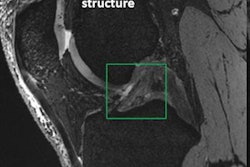

Soon after the U.S. Food and Drug Administration (FDA) cleared the first 7-tesla MRI scanner for clinical imaging, several institutions expanded their use of the modality to evaluate patients with neurological disorders, such as multiple sclerosis and epilepsy, and better diagnose musculoskeletal injuries. At the same time, clinicians became acutely aware of patients with implants and other accessories that might prevent the completion of a 7-tesla scan.

In this paper, Hoff and colleagues cited metallic implants as one primary complication with 7-tesla MRI, given their "high conductivity and low resistance to electric currents." Previous research has shown that 7-tesla scanning usually leads to minimal heating of implants, but surrounding tissue may experience increased heated due to relatively high electrical resistance. Implants and devices that are associated with nominal heating at 1.5- and 3-tesla "may trigger unsafe heating at 7-tesla," they noted.